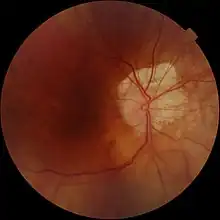

| Large myopic crescent in right eye with peripapillary choroidal atrophy. |

A myopic crescent is a moon-shaped feature that can develop at the temporal (lateral) border of disc (it rarely occurs at the nasal border) of myopic eyes. It is primarily caused by atrophic changes that are genetically determined, with a minor contribution from stretching due to elongation of the eyeball. In myopia that is no longer progressing, the crescent may be asymptomatic except for its presence on ocular examination. However, in high-degree myopia, it may extend to the upper and lower borders, or form a complete ring around the optic disc and form a central scotoma.

The myopic crescent is commonly seen in pathological axial myopia. The condition sometimes described erroneously as myopic choroiditis, but myopic crescent is not an inflammatory process and does not run parallel to the degree of myopia. It usually tends to occur after mid adult life. Myopic crescent is often associated with some degree of retinal degeneration and occasionally vitreous degeneration.